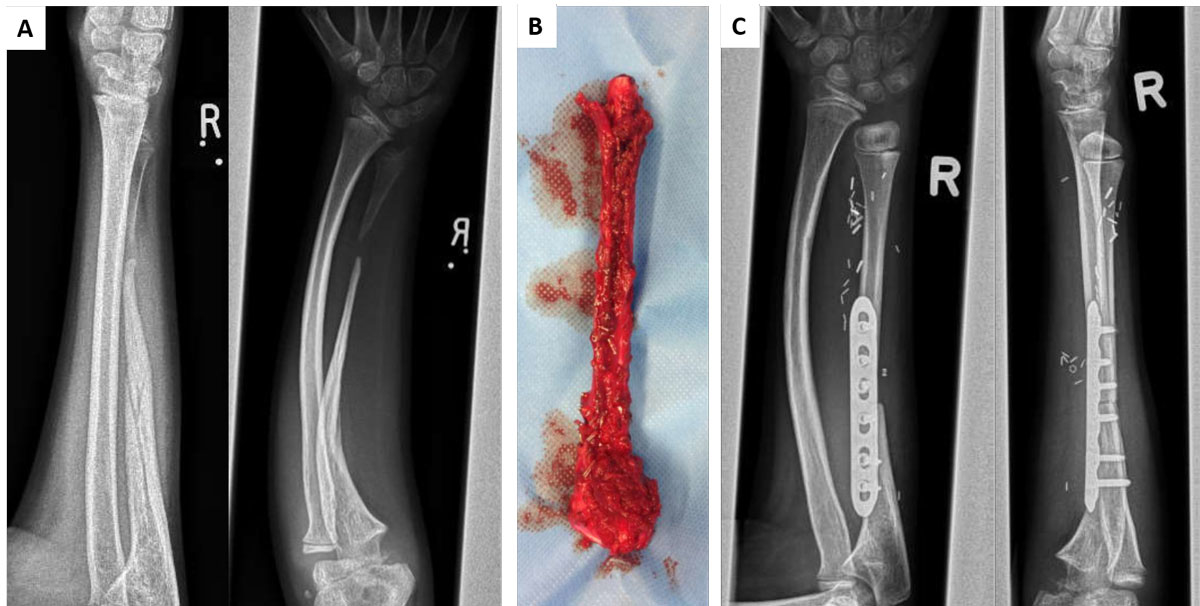

Defects in long bones also represent an unmet clinical need in children. These can be the consequence of cancer surgery, of congenital pseudoarthrosis of the tibia [22, 23] or abnormal bone mineralisation in genetic diseases such as neurofibromatosis. Even bagatelle traumas can result in pseudoarthrosis, with the need for bony reconstruction in an appropriate size. To date, autologous bone grafts harvested from another region of the body, such as the fibula, represent the state of the art (fig. 1). Depending on the size of the defect and, accordingly, the amount of graft material required, either donor site morbidity increases or the autologous bone available is not sufficient to treat defects with a reasonable risk-benefit ratio. For these high-risk bone defects, implantation of osteoprogenitor cells from various sources in combination with different materials has been tested by several groups [24, 25]. These approaches have been reported to be successful in a number of cases, though mechanical stability remains an important challenge.

Figure 1 Bone fracture complications due to neurofibromatosis. (A) Radiograph of a 12- year-old boy’s ulna after a minor trauma, with signs of a chronic non-union and deficient bone healing. Further investigation led to the diagnosis of neurofibromatosis type 1, which includes bone mineralisation abnormalities. (B) A long fibular graft including the growth plate was harvested to ensure safe reconstruction and preservation of balanced forearm growth. (C) The postoperative assessment indicates consolidation of the proximal ulna and an open epiphysis, although the positive result was achieved at the cost of extensive morbidity at the site of the fibula.